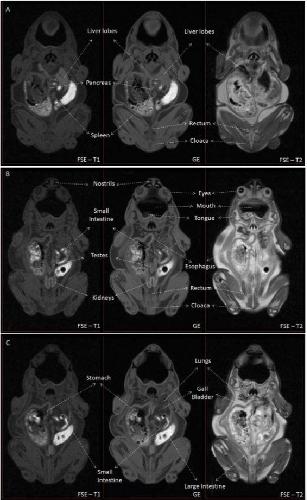

Figure S1 - MRI identification of structures contained in the coelomic cavity. Figure S1 shows the main structures identified in the coelomic cavity in Kaloula pluchra frog. Three different slices of the MRI experiment were selected (A, B, C). Three different MRI weightings (Fast Spin Echo T1-weighted, Gradient Echo and FSE T2-weighted) are shown for each slice.